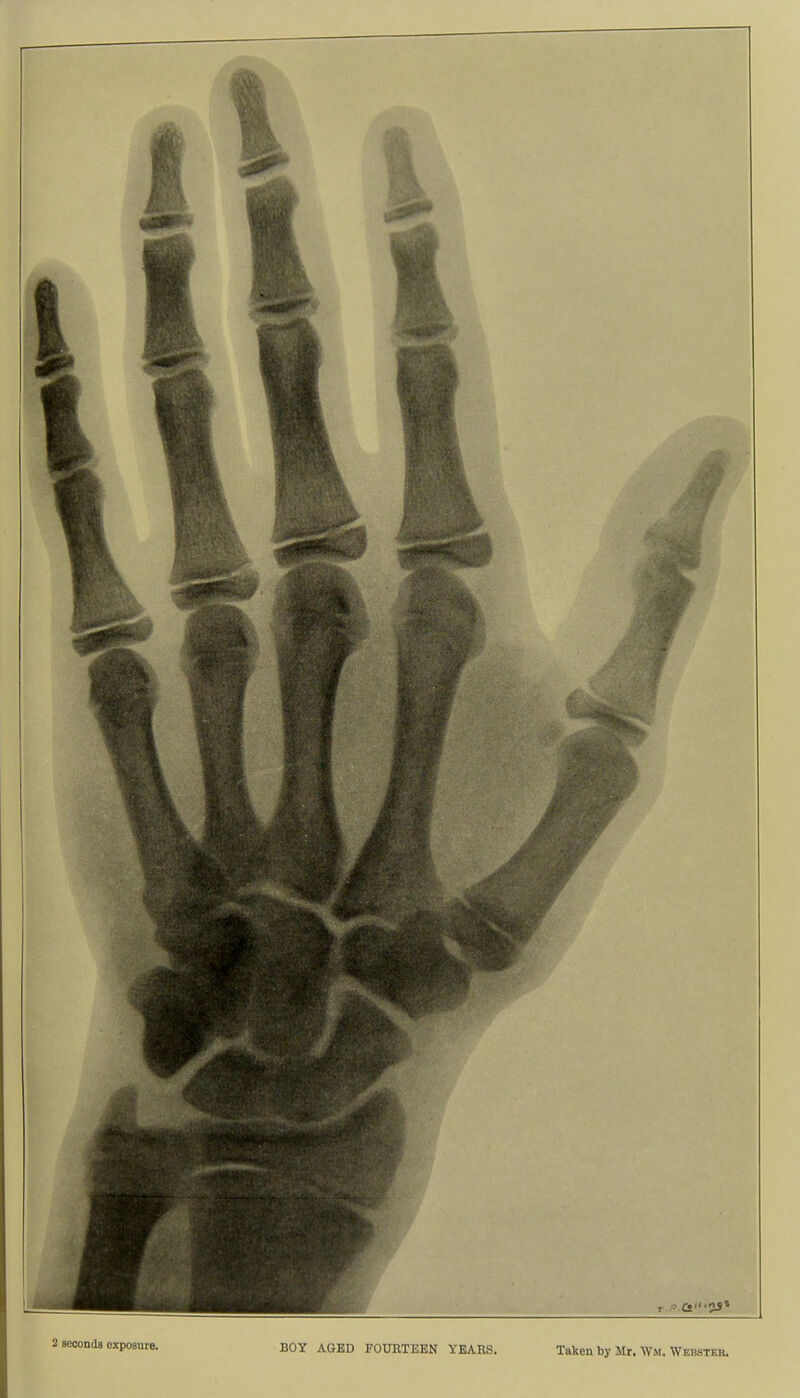

Skiagraphic atlas showing the development of the bones of the wrist and hand : for the use of students and others / by John Poland.

Credit: Skiagraphic atlas showing the development of the bones of the wrist and hand : for the use of students and others / by John Poland. Source: Wellcome Collection.